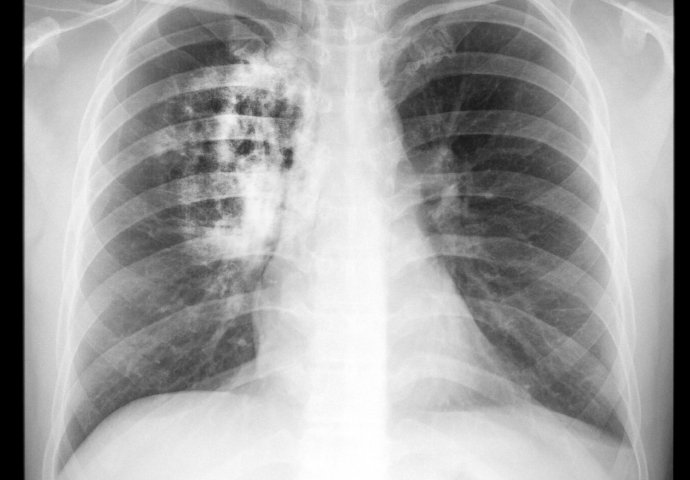

9 SIMPTOMA RAKA PLUĆA: Ovako vas tijelo upozorava na ovu bolest!

Osumnjivim simptomima razgovarajte sa svojim liječnikom obiteljske medicine, pogotovo ako su dugotrajni i ne možete ih ublažiti uobičajenim metodama.